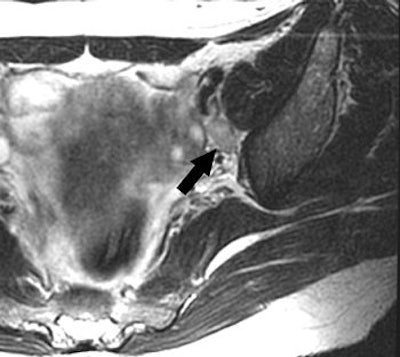

| A 48-year-old woman with true-positive left internal iliac lymph node metastasis in stage IIB uterine cervical cancer. MR axial T2-weighted fast spin-echo image (TR/TE, 5,000/68; echo-train length, 21) shows ovoid lymph node (arrow, 10-mm short-axis diameter) with smooth margin in left internal iliac area. |

According to the results, MRI showed 86 lymph nodes in total and histopathology revealed 17 metastatic lymph nodes in 55 patients. The authors found that the mean short-axis diameter of metastatic lymph nodes was larger than that of nonmetastatic lymph nodes. The sensitivity of this MR criterion was 33.3% and the accuracy was 91.4%.

"The prediction of nodal status was most accurate when a size criterion of greater than 9 mm was applied to the short-axis diameter of the lymph node," the group wrote.